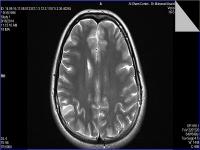

Medical imaging is an important investigative tool will help doctors to reach for the diagnosis of certain diseases, and the the advanced and high-quality imaging technologies are an important factor in maintaining the health of patients and accurate diagnosis of pathological lesions.